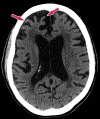

Neurodegenerative diseases are a devastating group of disorders that can be difficult to accurately diagnose. Although these disorders are difficult to manage owing to relatively limited treatment options, an early and correct diagnosis can help with managing symptoms and coping with the later stages of these disease processes. Both anatomic structural imaging and physiologic molecular imaging have evolved to a state in which these neurodegenerative processes can be identified relatively early with high accuracy. To determine the underlying disease, the radiologist should understand the different distributions and pathophysiologic processes involved. High-spatial-resolution MRI allows detection of subtle morphologic changes, as well as potential complications and alternate diagnoses, while molecular imaging allows visualization of altered function or abnormal increased or decreased concentration of disease-specific markers. These methodologies are complementary. Appropriate workup and interpretation of diagnostic studies require an integrated, multimodality, multidisciplinary approach. This article reviews the protocols and findings at MRI and nuclear medicine imaging, including with the use of flurodeoxyglucose, amyloid tracers, and dopaminergic transporter imaging (ioflupane). The pathophysiology of some of the major neurodegenerative processes and their clinical presentations are also reviewed; this information is critical to understand how these imaging modalities work, and it aids in the integration of clinical data to help synthesize a final diagnosis. Radiologists and nuclear medicine physicians aiming to include the evaluation of neurodegenerative diseases in their practice should be aware of and familiar with the multiple imaging modalities available and how using these modalities is essential in the multidisciplinary management of patients with neurodegenerative diseases.©RSNA, 2020.